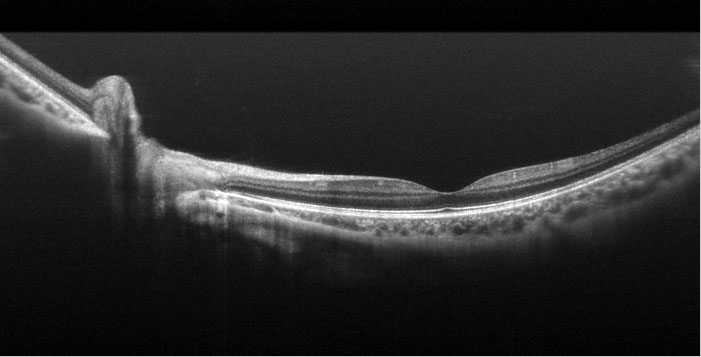

In vivo 3D imaging of Chicken Embryo

Gated Volumetric Imaging (Stage 17)

Maximum diastolic phase/Maximum systolic phase

Image on the left in frame: longitudinal cut, Image on the right in frame: cross-sectional cut